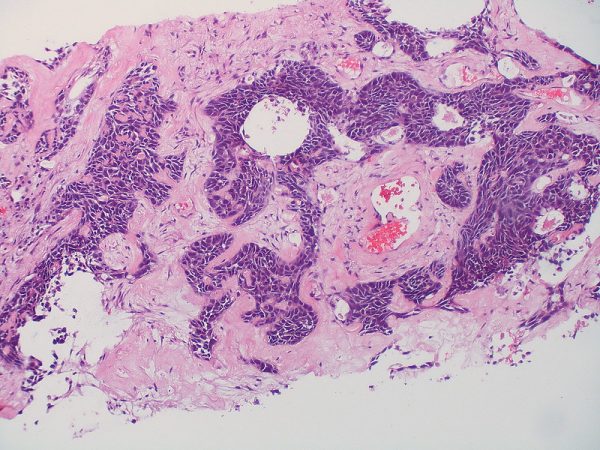

Τα παραπάνω επισήμανε στο in.gr o Παθολόγος-Ογκολόγος Νίκος Α. Κατιρτζόγλου, MDPhD μιλώντας για τον μη μικροκυτταρικό καρκίνο του πνεύμονα, τον τύπο της ασθένειας που αποτελεί το 80-85% των περιστατικών – τα υπόλοιπα περιστατικά αφορούν μικροκυτταρικό τύπο. Ο κάθε ένας από τους δύο τύπους καρκίνου πνεύμονα διαθέτει αρκετούς υποτύπους, ανάλογα με τα γονιδιακά τους χαρακτηριστικά που αποτελούν και τη μοριακή «υπογραφή» του όγκου.

Έτσι, στη κλασική χημειοθεραπεία (που και αυτή πλέον διαφέρει – ανάλογα με το εάν ο καρκίνος του πνεύμονα είναι αδενικού ή πλακώδους τύπου) έχουν προστεθεί οι στοχευτικοί παράγοντες (Στοχευμένη Θεραπεία), η αντι-αγγειογενετική θεραπεία και η ανοσοθεραπεία. Παραδοσιακά, ο πρώιμος καρκίνος πνεύμονα αντιμετωπίζεται μεχειρουργική θεραπεία, ενώ σε αρκετές περιπτώσεις εφαρμόζεται και η ακτινοθεραπεία, η οποία και αυτή έχει συγκεκριμένες ενδείξεις.

Επίτευγμα των τελευταίων ετών αποτελεί το γεγονός ότι η ανοσοθεραπεία, αναφορικά με το μεταστατικό στάδιο του ΜΜΚΠ, σε ορισμένες περιπτώσεις αντικατέστησε πλήρως την κλασική χημειοθεραπεία, σε άλλες χορηγείται σε συνδυασμό με αυτήν (με άλλοτε λιγότερους και άλλοτε περισσότερους κύκλους χημειοθεραπείας), ενώ ακόμα και ο τετραπλός συνδυασμός με δύο χημειοθεραπευτικά, έναν Ανοσοθεραπευτικό και έναν αντι-αγγειογενετικό παράγοντα είναι πλέον εγκεκριμένος.